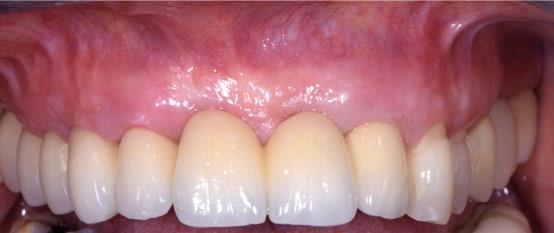

Entrega de la prótesis definitiva de metal-cerámica.

Detalle de los volúmenes obtenidos con el injerto conectival.

Comparación entre la situación pre y post-implante, destacando la modelación de los tejidos blandos lograda gracias a la cirugía mucogingival y a los perfiles protésicos.

Comparación entre la situación inicial y final.

A los 9 meses se entrega la prótesis definitiva de metal-cerámica, que se encuentra con perfiles ya correctamente modelados y maduros. La comparación entre la situación inicial y la final resalta cómo el restablecimiento solo de la parte supraósea ha sido suficiente para compensar un importante déficit volumétrico, sin necesidad de recurrir a complejas reconstrucciones óseas, cuyo resultado suele ser poco predecible. 